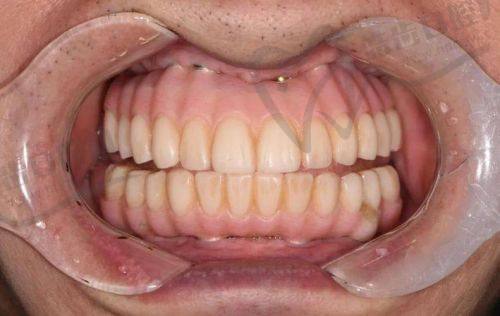

技术优势:医院拥有精良的口腔诊疗设备,如口腔显微镜、数字化口腔扫描仪等,为种植手术提供精细的诊断和治疗。医生团队由多名经验多的口腔骨干医生组成,他们在种植满口牙方面有着丰富的临床经验和独特的技术优势。采用精良的种植技术,如即刻种植、all-on-4种植等,缩短患者的治疗周期,提高患者的生活质量。